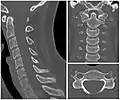

Cervical degenerative changes arise from conditions such as spondylosis, stenosis of intervertebral discs, and the formation of osteophytes. The changes are seen on radiographs, which are used in a grading system from 0–4 ranging from no changes (0) to early with minimal development of osteophytes (1) to mild with definite osteophytes (2) to moderate with additional disc space stenosis or narrowing (3) to the stage of many large osteophytes, severe narrowing of the disc space, and more severe vertebral end plate sclerosis (4).[5][6][7]